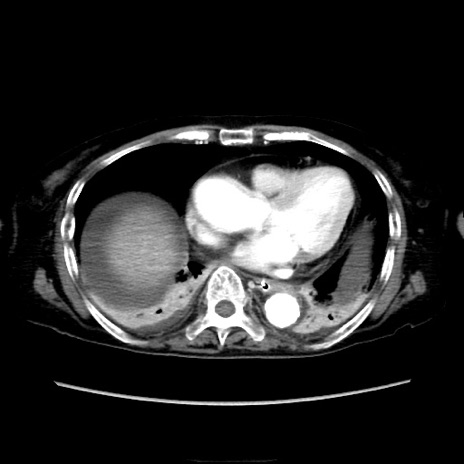

症例40(横断像)

他院CT